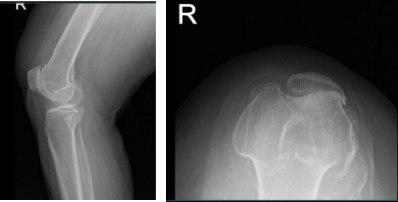

Patient is a 56 year-old female and has been experiencing right knee pain for almost a week. She is currently working but has to stop because of the knee pain. Considering acute pain with no relief in the last 2 weeks and she is unable to carry out activities of daily living we agreed to do a stat MRI of the knee.

Aside from this, I prescribed Relafen for anti-inflammatory. X-ray and MRI results were presented in the office. X Ray results showed moderate osteoarthritic degenerative changes and slight.

MRI of right knee

MRI result impression as follows: Bone marrow edema at the anterior peripheral aspect of the medial tibial plateau with slight flattening and irregularity of the articular surface there is a low-grade healing subchondral impaction or stress fracture.

Complex tear of the posterior horn medial meniscus including a displaced meniscal flap abutting the posterior root and measures 1 cm in length. Severe patellofemoral arthrosis. Moderate femorotibial arthrosis. Moderate joint effusion.